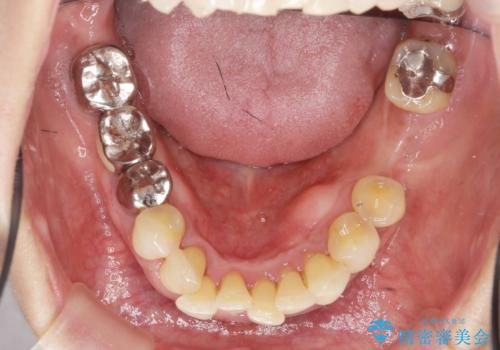

- 下顎前歯のグラつきがどんどん悪くなり、痛くて噛めなくなってきたことの改善を希望され来院されました。

下顎前歯の1本は前歯よりも前に出てしまい後ろからの力を受けることで、周囲の骨も吸収しグラつきも大きくみられます。